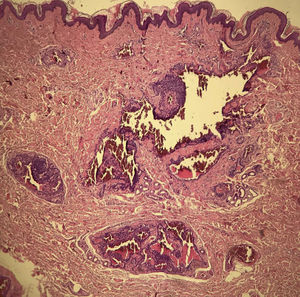

A 35-year-old male patient complained of a painful angiomatous nodule on the lateral aspect of the left arm for about eight years (Fig. 1). He reported worsening of the pain with exposure to cold and digital pressure. Love’s test was positive and Hildreth’s test was not performed due to the anatomical difficulty in properly positioning the tourniquet. Dermoscopy revealed purplish lagoons circumscribed by a pale halo next to a pink area without structures (Fig. 2). Surgical excision of the lesion was performed and histopathological confirmation of extradigital glomus tumor (EGT) was attained. The histopathological analysis showed intradermal nests of monomorphic cells, with rounded nuclei, organized in single or multiple cords around vascular structures (Fig. 3). In the center of the histological section, one of these nests can be seen, showing exuberant size in relation to the others (Fig. 4). There has been no recurrence after two years of follow-up.

SGT consists of nests of uniform grouped glomus cells, without prominent vascularization or exuberant smooth muscle tissue. Tumors with differentiation and the significant presence of smooth muscle tissue are subclassified as glomangiomyomas. Glomangiomas show intradermal nests of monomorphic glomus cells, with rounded nuclei, organized as single or multiple cords, around exuberant vascular structures.1,2,4,6 The description is consistent with that of the present case (Fig. 3). The prevalence of glomangiomas is highest among extradigital tumors.1

The dermoscopic finding of a purplish area without structures, previously described in the literature, was found in SGT lesions constituted by a cohesive tumor with a more abundant cell component in relation to the vascular spaces. This histopathological organization is reflected in the observed dermoscopic findings.4 In glomangiomas, the large vascular structures surrounded by delicate cell cords may stand apart and stand out individually (Fig. 4), originating the purplish lagoons described in this study. Thus, the authors believe that it is not only a dermoscopic finding associated with EGT, but it also indicates a specific subtype: glomangioma. Despite the limitation of conclusions from a single case, this new dermoscopic finding can complement the investigation and increase the accuracy of the diagnosis of EGT.